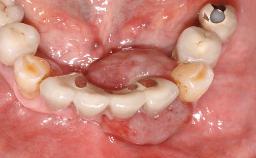

The fracture of an implant after it has been restored is one of the most severe complications. It most frequently occurs in partially edentulous jaws (1.5%). Most implant fractures involve implants with a diameter of 3.75 mm made of commercially pure titanium (Eckert 2010). Unfortunately, many cases are not reported or documented by the clinicians involved in resolving the problems created by the fracture. This case report describes the management of an implant fracture at site 36 in a middle-aged male patient. The implant had been restored with a screw-retained metal-ceramic crown.